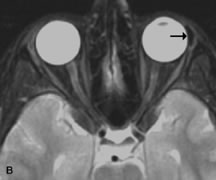

PATIENT PREPARATION Before MRI is performed, patients must be screened and prepared to avoid the potential hazards associated with the strong magnetic field. Patients who have ferrous aneurysm clips or cardiac pacemakers, who depend on life-support equipment, or who retain a possible metallic intraocular foreign body are not candidates for this imaging modality. MRI cannot be performed on obese patients who cannot fit into the bore of the magnet. Patients who are claustrophobic may not tolerate a prolonged period of study within the confines of the magnet, whereas others might do well if given a mild sedative. All worn metallic objects (e.g., necklaces, watches) should be taken off, credit cards set aside, and eye makeup removed before entering the room containing the magnet.5,20,34,35,36 NORMAL ORBITAL ANATOMY T1-weighted images provide the best anatomic details of the orbit because they display superior contrast resolution between normal structures (see Fig. 8). The vitreous has a long T1, resulting in an intermediate signal similar to brain, whereas the crystalline lens and sclera appear dark because of a longer T1 and short T2. The extraocular muscles, like all skeletal muscles, demonstrate a moderately long T1 and short T2 and highly contrast with the intense signal of the surrounding orbital fat (adipose tissue has an extremely short T1). The lacrimal glands appear as mottled areas of reduced intensity of the signal from the orbital fat in the lacrimal fossa. The optic nerves are seen with the same signal intensity as brain white matter and are hypointense relative to the orbital fat because their Tl is longer than the Tl of fat but shorter than the Tl of water. Cortical bone is not well delineated because it contains little free water, yielding minimal signal in MRI, and thus appears dark on all pulse sequences. This feature explains why MR images of the orbital apex and intracanalicular portion of the optic nerves are superior to comparable CT scans. Partial volume averaging of the bones in these regions obscures soft tissue details on CT images, whereas MRI reveals the signals only from the soft tissue structures with no cortical bone input. Bone marrow, on the other hand, is seen as a relatively intense signal because of its high fat content (see Fig. 8).37,38 T2-weighted pulse sequences are not ideal for imaging normal anatomy; however, they are particularly useful in revealing pathologic conditions (see Fig. 9). T2-weighted studies are most easily recognized by a bright vitreous signal. ORBITAL DISEASES Vascular Lesions Cavernous hemangiomas appear as well-circumscribed, smooth, usually intraconal masses that are isointense to muscle on T1-weighted images and hyperintense on T2-weighted images (Fig. 12). Patchy early enhancement is typically followed by diffuse, more homogeneous enhancement.39 The internal architecture of the mass, including septation and internal vasculature, may often be appreciated with high-quality orbital imaging.40 Lymphangiomas consist of ectatic vascular channels within a connective tissue stoma with varying degrees of lymphoid cellularity. On MRI, these tumors are typically poorly circumscribed, multicompartmental, and heterogeneous, often showing cystic dilations with fluid levels (Fig. 13). The signal characteristics within lymphangiomas vary considerably, reflecting cystic and solid components and the varying paramagnetic characteristics of blood at different stages of degradation.40–42 Acute hemorrhage appears hypointense on both T1- and T2-weighted formats. Methemoglobin present in subacute hemorrhage (3 to 14 days) leads to hyperintense signal on both T1- and T2-weighted images.41 A small percentage of lymphangiomas appear radiologically indistinct from orbital cavernous hemangiomas.43 Orbital varices are venous malformations that expand with increased systemic venous pressure, such as with Valsalva maneuvers. Because rapid acquisition of images during a Valsalva maneuver is important in imaging such a lesion, conventional or spiral CT is currently the modality of choice.44 MRI is an excellent modality for demonstrating enlargement of the cavernous sinus and dilation of the superior ophthalmic vein in patients with high-flow carotid-cavernous fistulas (Fig. 14).37MRA may be helpful in the evaluation of the venous outflow pattern. The rapidly flowing blood in these vascular structures carries the excited protons out of the section before they can be imaged, resulting in their dark appearance.5 In low-flow dural arteriovenous malformations, MRA may help define the arterial feeding vessels.45 Neural Lesions MRI is more effective than CT in delineating the intracranial optic nerves, chiasm, and optic tracts and, for this reason, is the preferred imaging modality in the evaluation of optic nerve disorders. The spatial relationships and image contrast of the orbital tissues with intraorbital optic nerve tumors is comparable between the two imaging modalities. The normal nerve is isointense to brain and appears enlarged and kinked owing to infiltration of an optic nerve glioma on T1-weighted images. Gliomas appear hyperintense on T2-weighted images and may be heterogeneous owing to cystic areas within the tumor. Contrast enhancement is variable.46 Intraorbital and intracranial optic nerve sheath meningiomas are usually isointense to cortical gray matter on Tl-weighted images and remain isointense on proton density studies (Fig. 15). Gd-DTPA is useful in delineating the intracranial extension of optic nerve meningiomas.7,47 The hyperostosis of bone and calcification associated with meningiomas are not demonstrated as well on MRI studies as on CT scans.20,37 Gd-DTPA–enhanced MRI also appears promising in the study of the permeability of the blood–brain barrier in selected optic neuropathies.22,48 MRI may reveal an enlarged optic nerve and some degree of contrast enhancement in cases of optic neuritis.49 Muscle Disorders Extraocular muscle enlargement in patients with thyroid-associated orbitopathy is demonstrated equally well with CT and MRI studies. However, the superior tissue contrast on MR images reveals better details of the relationships of the optic nerve to the thickened muscles at the orbital apex (Fig. 16).50 In addition, MRI may be able to differentiate between muscles that are enlarged as a result of edema and active inflammation and those enlarged because of fibrosis by their T2 relaxation times.21 Quantitative MRI was not found to be accurate in predicting the success of low-dose orbital irradiation.51 However, a muscular index relating the diameters of the rectus muscles to the bony orbital dimensions was useful in predicting optic nerve compression.52 MRI is also effective in imaging orbital tumors of mesenchymal origin, such as rhabdomyosarcoma, particularly in the assessment of extension into the anterior and middle cranial fossae (Fig. 17).37 The lack of any pathognomonic radiologic features necessitates rapid orbital biopsy when rhabdomyosarcoma is suspected. Osseous Lesions In general, CT is the imaging modality of choice when details of quantity and quality of bone are needed; however, abnormalities of bones can be detected indirectly by MRI. Cortical bone appears black (signal void) on MR images because of its low proton density and free-water content. The absence or discontinuity of the signal void of the orbital walls may represent bony destruction or fracture. Hyperostosis associated with prostate metastases or meningioma is visualized as areas of black smudging.50,53 Diseases in which the bone is replaced by pathologic tissues with a high free-water content, such as fibrous dysplasia, are well demonstrated on MRI. An intermediate signal intensity on T1-weighted images and hypointense signal on T2-weighted images is representative of fibrous dysplasia. Enhancement on post–Gd-DTPA MR scans is seen and is more evident in areas that are less mineralized.54 Cystic Lesions Dermoid cysts appear as rounded, well-defined lesions typically contiguous with an orbital bony suture. The high-intensity signal on T1-weighted images is attributed to the sebaceous-produced lipid contents (Fig. 18).31,50 Mucoceles may demonstrate a hypointense or hyperintense signal on MR images, depending on the concentration of proteinaceous or inflammatory fluid components. The integrity of the bony walls of the expanded sinus cavities cannot be assessed on MR as well as by CT.37,50,55,56 A high-signal intensity on Tl- and T2-weighted images is characteristic of orbital chronic hematic cysts because of the blood-breakdown products within the cysts.57 Trauma Although soft tissue relationships are usually better demonstrated on MRI, the evaluation of craniofacial bony trauma is preferable with CT. For example, prolapse of orbital fat through a fracture site and hemorrhage of adjacent tissues are demonstrated in an MR image, but the actual fractured bone is not imaged. Three-dimensional MRI of the orbit in subacute trauma has been described,58 although its precise role is not currently established. MRI has been suggested to be superior to CT in detecting intraorbital wooden foreign bodies.59,60 In a series of penetrating orbital injuries with organic foreign bodies, however, MRI was able to identify the foreign body in only four of seven cases.61 With an in vitro model for wood foreign body, McGuckin and colleagues concluded that CT was the imaging modality of choice.62 A careful history and, in selected cases, plain films to rule out a metallic foreign body are crucial before MRI is considered in patients with periocular trauma. MRI is particularly helpful in the detection and characterization of subperiosteal hematomas of the orbit (Fig. 19). They are most commonly seen in the subperiosteal space of the superior orbit as well-defined masses following a traumatic injury. The signal intensity varies depending on the acute, subacute, or chronic nature of the hematoma, based on the stage of blood degradation. Fresh hemorrhages are hypointense on T1-weighted images and hyperintense on T2 images. Hematomas that are 1 to 7 days old are hypointense on both T1- and T2-weighted images. T1-weighted images of hematomas more than a week old are hyperintense due to the oxidation of deoxyhemoglobin to methemoglobin, whereas the T2 images remain hypointense.63 Metastatic Tumors Breast carcinoma metastatic to the orbit has been demonstrated to be hypointense to the surrounding orbital fat on T1-weighted studies and hyperintense on T2-weighted images and has an affinity to the extraocular muscles (Fig. 20).50,64 The MRI characteristics of prostate carcinoma metastatic to the orbit have been described as involving the greater and lesser wing of the sphenoid, orbital roof, and optic canal. Diffuse bone hypertrophy with isointense or slightly hyperintense tissue on T1-weighted images represents the osteoblastic carcinomatous bone infiltration. Contrast enhancement is variable on T1-weighted and fat-suppressed images.65 Most other metastatic tumors also have a lower intensity signal on T1-weighted images and appear to displace or infiltrate normal orbital structures; however, their signal characteristics are variable on T2-weighted MR images.66 Many metastatic tumors demonstrate bright contrast enhancement with Gd-DTPA. Infectious Disorders MRI findings of preseptal and orbital cellulitis typically include increased signal intensities on T2-weighted images of the eyelids and orbital fat, respectively, due to the increased water content of the tissues. Since most cases of bacterial orbital cellulitis are associated with paranasal sinusitis, hyperintense signals of the affected sinuses may also be found on T2-weighted images as well as enhancement of polyps and granulation tissue on postgadolinium T1-weighted MR images. Subperiosteal abscess formation may occur due to contiguous spread of infection from the paranasal sinuses and appear on MRI as an area of intermediate signal on T1-weighted and proton-weighted MR images. The abscess may appear slightly hyperintense compared with muscle on T2-weighted scans with the necrotic contents having the greatest intensity.67 MRI and MRV are more sensitive than CT in revealing cavernous sinus thrombosis. Engorgement of the cavernous sinus, extraocular muscles, and ophthalmic veins is seen with hyperintensity of the thrombosed sinuses evident on all pulse sequences. The enlarged, thrombosed superior ophthalmic vein appears less hypointense than the normal contralateral ophthalmic vein, and hyperintensity within the lumen of the vessel may be seen on T1- and T2-weighted MR images.68 Inflammatory and Lymphoproliferative Lesions Inflammatory conditions of the orbit, both idiopathic (inflammatory pseudotumor) and those of known causes, have been found to be hypointense to fat and isointense to muscle on Tl-weighted studies and isointense or slightly hyperintense to fat on T2-weighted images (Fig. 21).50,64,69 The more fibrous or sclerosing varieties have less signal intensity on T2-weighted images. Marked enhancement is seen in pseudotumor infiltrates after gadolinium administration.70 The same signal characteristics are demonstrated in patients with Tolosa-Hunt syndrome, with mass lesions seen in the cavernous sinuses and orbital apices.71 Lymphomas have MRI characteristics similar to those of inflammatory lesions in that they are hypointense to fat and isointense to muscle on T1-weighted images (Fig. 22). They may appear hyperintense to fat on T2-weighted images, perhaps owing to less fibrosis than that seen in orbital inflammatory pseudotumor, although this is not a consistent finding.31,50,66 Lymphoid tumors typically enhance moderately after contrast injection. Unfortunately, studies have shown that tumor density and homogeneity are similar between inflammatory and malignant orbital infiltrates, and MRI cannot differentiate these lesions.72,73 Lacrimal Gland Tumors Lacrimal gland lesions present special problems in diagnosis and management. Pleomorphic adenoma (benign mixed tumor) should not be biopsied, but rather excised in toto. On the other hand, for lymphoma and inflammatory infiltrates, incisional biopsy is more appropriate than complete excision of the lacrimal gland. Thus, preoperative clinical and radiologic evaluation are especially crucial in planning appropriate surgical management. Pleomorphic adenomas demonstrate long T1 and T2 signal characteristics. They may show heterogeneity on T2-weighted images74 and moderate to marked enhancement with contrast.75 Signal characteristics of adenoid cystic carcinoma include hypointensity to fat on T1-weighted images, hyperintensity to fat with increased T2 weighting, and isointensity to fat on proton density-weighted studies (Fig. 23).31,75 Secondary bony alterations of the lacrimal fossa associated with lacrimal gland tumors, such as remodeling (benign mixed tumor) or destruction (adenoid cystic carcinoma), are seen indirectly on MR images; however, bone windows on CT scans provide better delineation of these changes. In contrast to the round or globular appearance of benign or malignant epithelial tumors of the lacrimal gland, lymphoproliferative tumors usually appear to be molding or draping onto the globe and the surrounding bony orbit. LACRIMAL DRAINAGE SYSTEM DISORDERS MRI with surface coils provides excellent spatial resolution and tissue-specific signal intensities of the lacrimal drainage system. These parameters have been found useful to more accurately demonstrate the extent of lesions in the lacrimal sac and differentiate long-standing mucoceles from solid tumors than CT.76 Physiologic studies in patients with tearing disorders now include MR dacryocystography, in which Gd-DTPA is either placed topically in the conjunctival fornix or injected by cannulation into the lacrimal sac. They provide a detailed morphologic and functional analysis of the lacrimal excretory system; however, they are no more sensitive than digital-subtraction dacryocystography or CT dacryocystography.77–79 INTRAOCULAR TUMORS On MRI, uveal melanomas have a typical appearance that helps to differentiate them from other primary and secondary intraocular tumors as well as choroidal detachments. Pigmented melanomas are hyperintense on Tl-weighted images, hypointense on T2-weighted studies, and hyperintense on proton density–weighted examinations (Fig. 24).30,31,50,80–82 These signal characteristics have been attributed to the paramagnetic properties of melanin because of stable free radicals that shorten the T1 and T2 relaxation times. Moderate enhancement is seen on postgadolinium T2-weighted images. Gadolinium-enhanced T1-weighted images are particularly sensitive in detecting choroidal melanomas.83 MRI may be less sensitive in detecting extrascleral extension of tumor than echography performed by an experienced ultrasonographer.84 Tumors metastatic to the choroid are hyperintense on T1- and T2-weighted images.24 The signal characteristics, however, may be similar to those seen with choroidal melanoma. Choroidal hemangiomas, on the other hand, have an intermediate signal on T1-weighted sequences and become hyperintense on T2-weighted images50 as well as proton density–weighted images.81 Retinoblastomas display moderate signal intensity on T1-weighted studies and a low signal on T2-weighted images.31,80,85 Calcification can be easily detected by CT and ocular ultrasonography but is not imaged by MRI.25,50 The presence of optic nerve involvement is best evaluated by MRI. ACQUIRED ANOPHTHALMIA When an eye is removed owing to tumor or trauma, an implant is typically placed in the intraconal space. MRI may be useful in defining the size, shape, and position of such orbital implants.86 Porous hydroxyapatite or polyethylene implants are preferred by many surgeons performing enucleation or evisceration. A porous implant offers the possibility of supporting a motility coupling peg to increase the movement of the overlying prosthesis. MRI with contrast is used by some surgeons to evaluate the degree of fibrovascular ingrowth in hydroxyapatite87 and porous polyethylene88 implants prior to motility peg placement. |